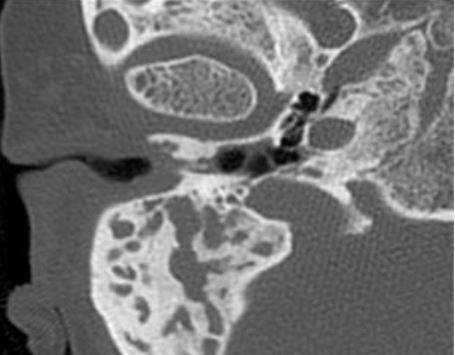

КТ (А) и МРТ(В) - картина холестериновой гранулемы

Эта дилемма волнует многих пациентов, но вид исследования выбирает лечащий врач, опираясь на результаты предыдущей диагностики и на конкретные жалобы. Отказываться от КТ уха из-за ложных соображений о вреде процедуры не стоит, современные мультидетекторные томографы позволяют минимизировать влияние лучевой нагрузки для большей категории лиц (исключение - беременные и дети, не достигшие 14 лет). В ряде наблюдений, особенно, если визуализируется опухолевый процесс, может понадобиться и МРТ, и КТ уха - эти способы взаимодополняют друг друга. Выполнение магнитно-резонансного сканирования обосновано, если после проведенной КТ остались сомнения в диагнозе. МРТ лучше демонстрирует менингоцеле, холестеатому, неврит лицевого нерва, внутричерепную патологию, вызванную процессами в среднем ухе, что не всегда показывает компьютерная томография высокого разрешения. КТ среднего уха часто не способна визуализировать степень возможной облитерации улитки после перенесенного воспаления или отдаленные последствия перелома височной кости. Точная оценка состояния имеет решающее значение для планирования кохлеарной имплантации.